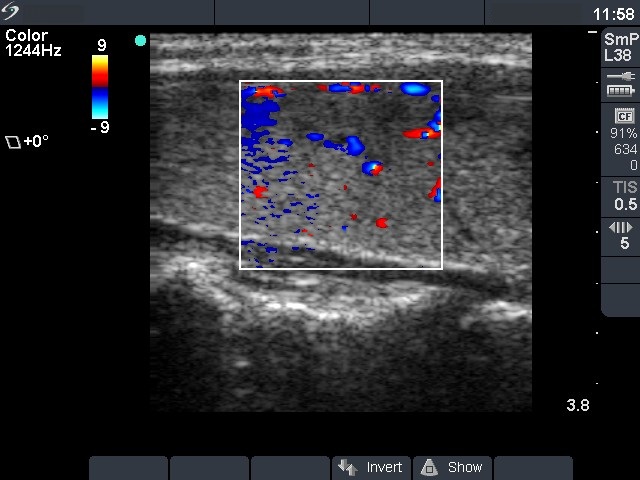

Follow-up investigation 18 months after first visit (ultrasonographic picture 3)

Patient on daily 5 mg methimazole therapy in euthyroid state

Right lobe, longitudinal scan, color Doppler method. The vascularization is average.